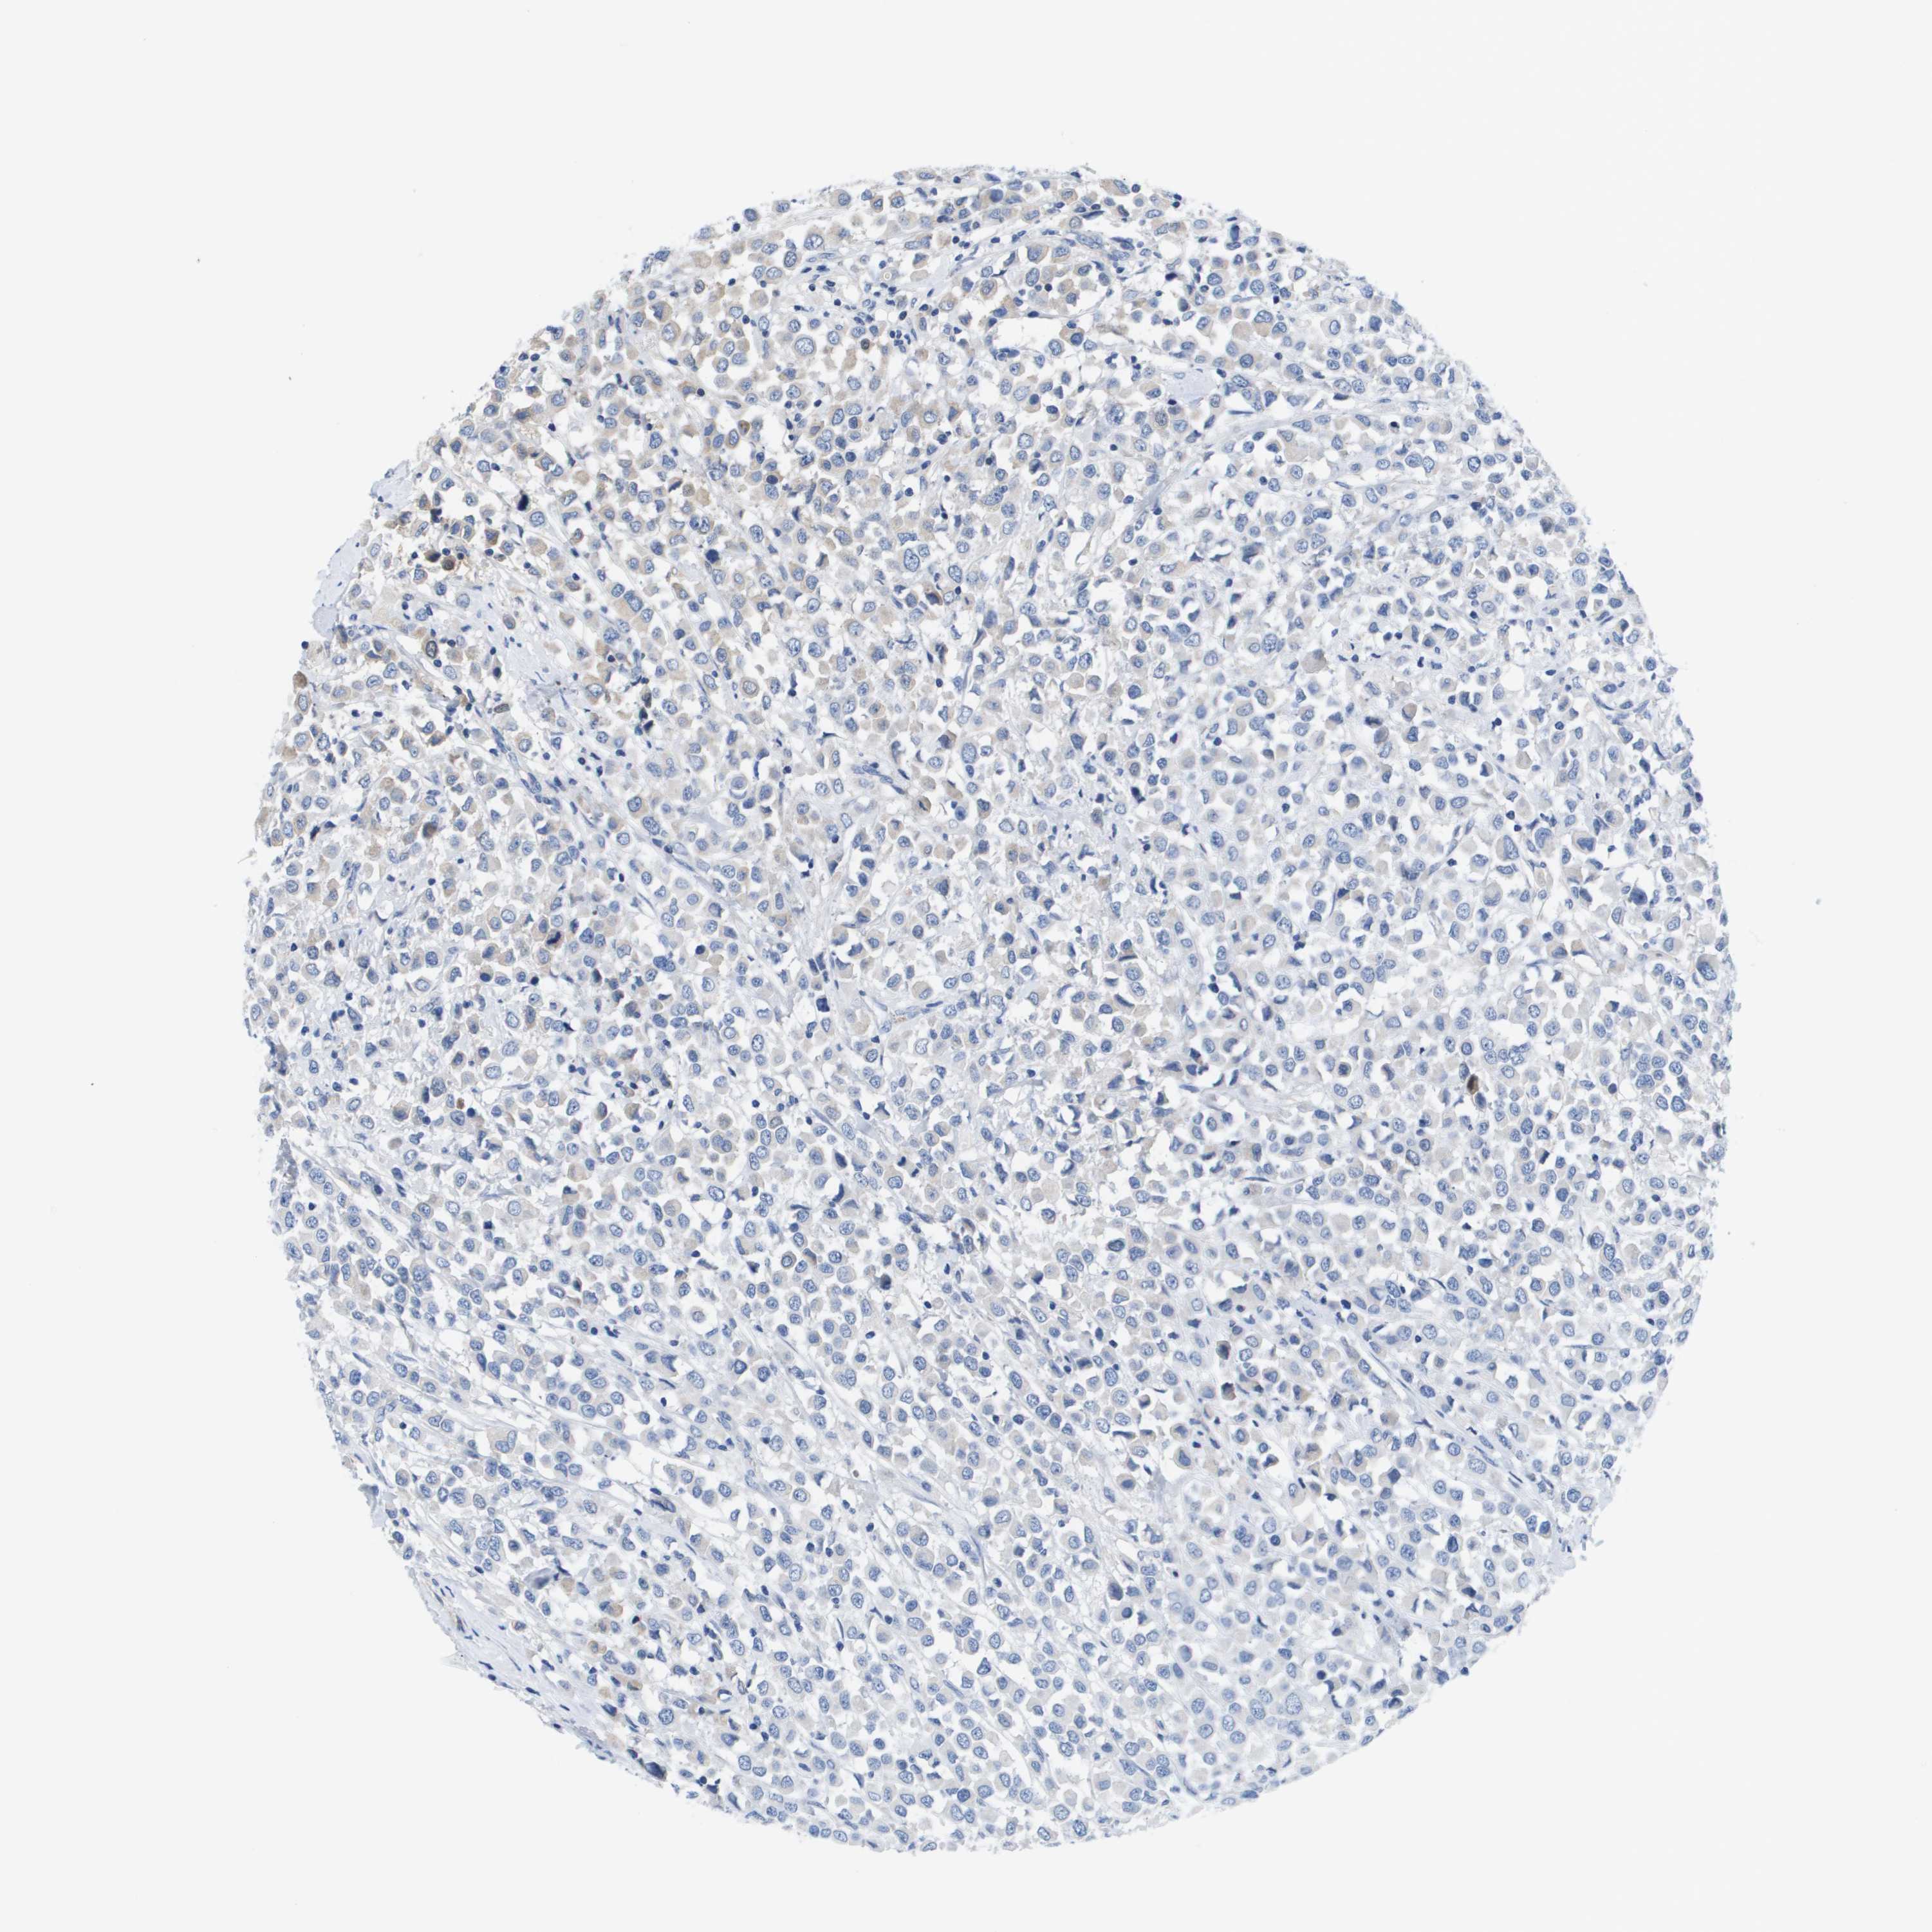

BRCA TCGA BRCA VALIDATION PROTEIN EXPRESSION

ANTIBODIES

AND

VALIDATION